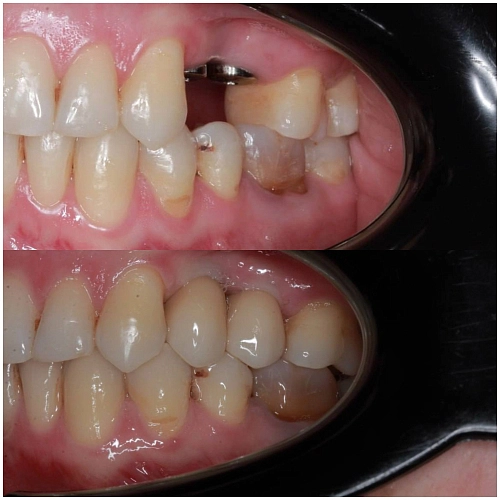

На фото работа врача-ортопеда Андреева ДП